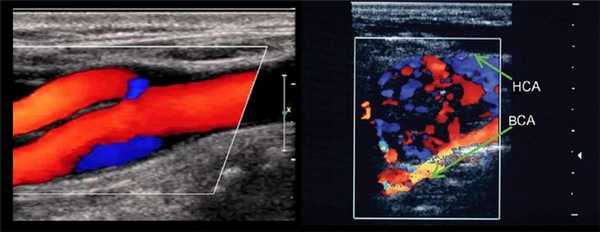

Что лучше МРТ или УЗИ сосудов шеи?

Ультразвуковая диагностика базируется на способности волн проходить через ткани различной плотности и отражаться с определенной скоростью. Это и есть «эхо», которое регистрирует датчик. Затем компьютерная программа преобразует сигнал в изображение.

УЗИ сонной артерии в месте бифуркации

Что лучше, МРТ или УЗИ, для диагностики патологий шейных сосудов, определяет врач. Оба метода считаются абсолютно безопасными и нужными. УЗИ занимает меньше времени и не требует ограничений подвижности, тогда как МРТ дает более полные сведения о состоянии всех структур шейного отдела. Ультразвуковые методики подходят для экспресс-диагностики, а томография оптимальна для выяснения природы заболевания и сбора дополнительных сведений.

Врачи предпочитают УЗИ, если для определения патологии решающее значение имеет скорость кровотока в сосудах шеи. МРТ предоставляет важную информацию, если есть подозрения на поражения стенок артерий/вен или мягких тканей, которые могут привести к острым нарушениям мозгового кровообращения.